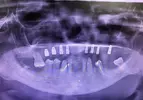

Implant tedavisi